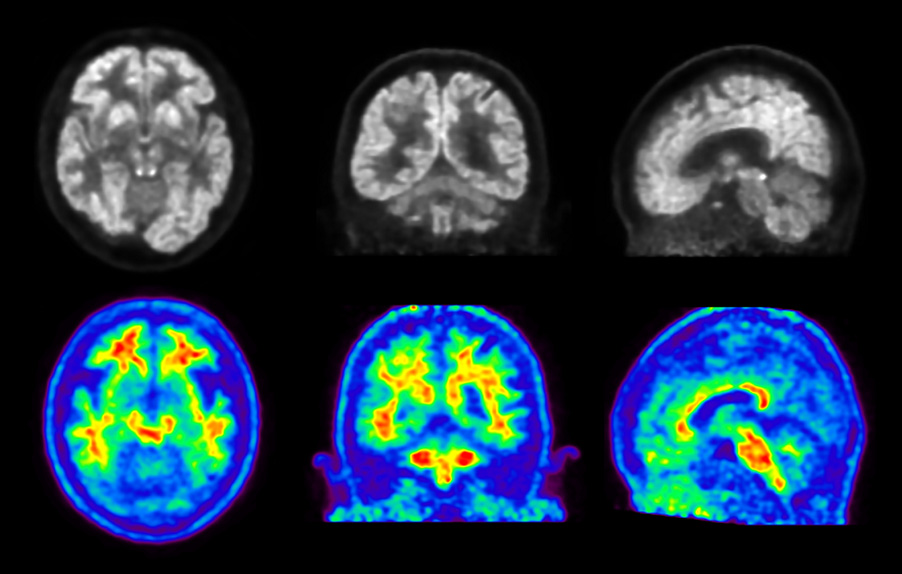

Head / Case6 : FDG and Amyloid

Courtesy :

Kindai University Hospital

Imaging protocol

Injected dose

: 3.46 MBq/kg, 18F-FDG

Uptake time

: 68 minutes

Scan time

: 30 minutes